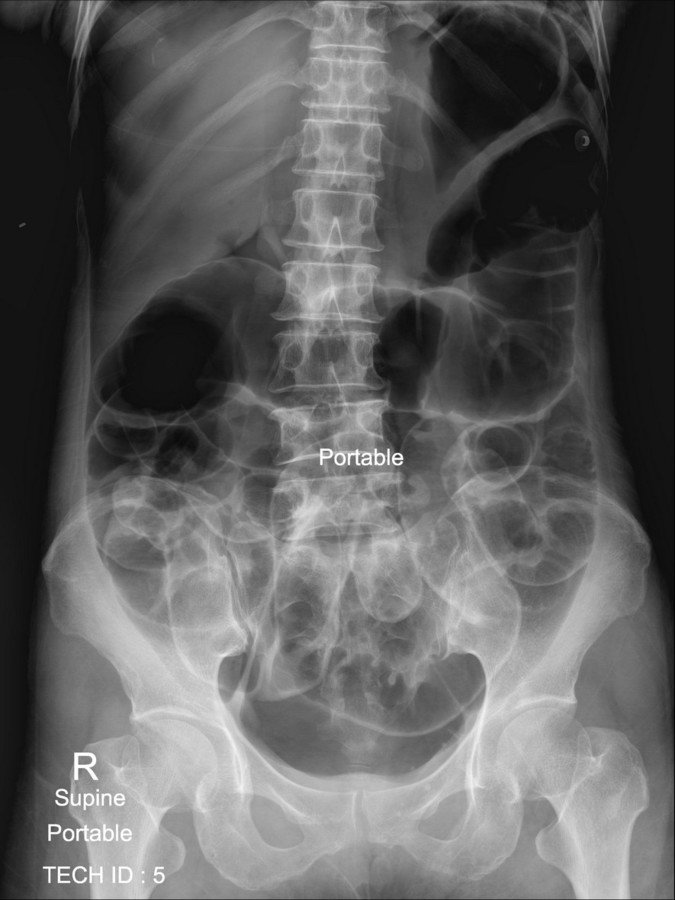

History :  A 60-year-old man. The patient had colonography and polypectomy with abdominal pain

The salient abnormality in this film?

D. All answers correct:

Large and small bowel dilatation due to post colonography

- Free air due to

rupture of the colon

Abdominal Radiograph :

* Free air can be detected on an abdominal radiograph

* Important signs on supine film include:

Plain abdominal radiograph :

Double wall sign

Lucent liver sign

Lateral umbilical ligament sign (inverted "V" sign)